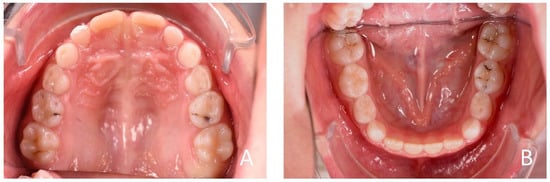

3.1. Clinical Case #1

3.2. Clinical Case #2